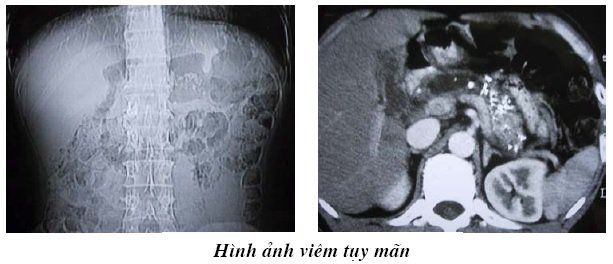

Chụp cắt lớp vi tính viêm tụy mãn

Cụ thể hơn, hình ảnh viêm tụy mạn tính khi chụp cắt lớp vi tính viêm tụy có thể nhìn thấy rất rõ kể cả khi không tiêm thuốc cản quang vẫn thấy được hình ảnh vôi hóa, hình ảnh sỏi trong ống tụy cũng như sự lan tỏa hay khu trú của tổ chức viêm. Về kích thước của tụy cũng có những thay đổi nhất định, bệnh nhân viêm tụy mãn khi chụp cắt lớp vi tính viêm tụy có thể thấy kích thước tụy to ra hoặc nhỏ hơn so với bình thường, cần phân biệt với những trường hợp tụy của người già bị teo nhỏ hay trường hợp tụy to ra đối với những khối u đặc.

Một đặc điểm khác đó là ống Wirsung bị giãn ra, dựa vào đặc điểm này chia viêm tụy thành 3 thể bệnh theo Kasugai như thể nhẹ có ống Wirsung bình thường với một vài vòng nối bị bất thường, thể vừa xuất hiện dấu hiệu ống Wirsung không đều và thể nặng có tình trạng ống tụy bị hẹp, tìm thấy sỏi trong ống tụy, giả nang tụy và cả hiện tượng hẹp ống mật chủ. Nếu có nang tụy thì khi chụp cắt lớp vi tính viêm tụy sẽ khảo sát được kích thước và số lượng nang, những đặc điểm cấu trúc bên trong của nang. Trường hợp bệnh nhân có những triệu chứng đau dữ dội do bị viêm nhiễm thần kinh thận tạng thì khi chụp cắt lớp vi tính sẽ thấy được tình trạng thận tạng bị chèn ép hay có sự thâm nhiễm không đồng đều về tổ chức mỡ phía sau tụy.